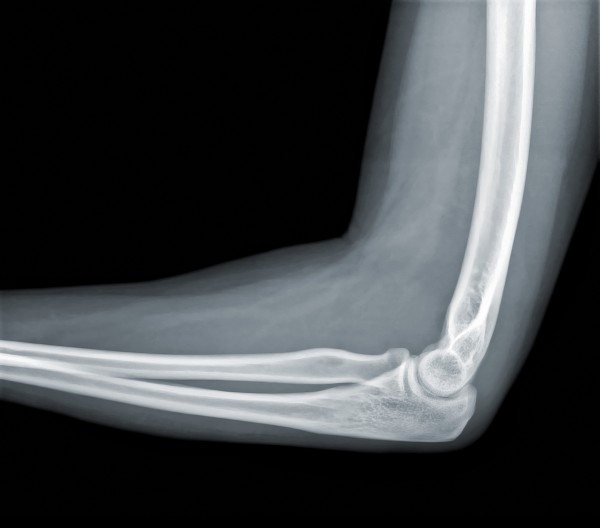

Anatomy of the Elbow

The elbow is comprised of the humerus, radius, and ulna bones that articulate at three joints: the humero-radial, humero-ulnar, and radio-ulnar joints.

The synovial joints of the humerus act as hinges to bend and straighten the elbow while the radio-ulnar joint is a pivot joint that allows forearm rotation (in other words, palms up or down).

The joints are stabilised by the radial and ulnar collateral ligaments that run on either side of the joint; and the annular ligament, a ring-like ligament that wraps around the radius and attaches at the ulna.

Finally, the subcutaneous, intra-tendinous, and subtendinous olecranon bursa are fluid-filled sacs that reduce friction and allow the joint to glide when the elbow moves.